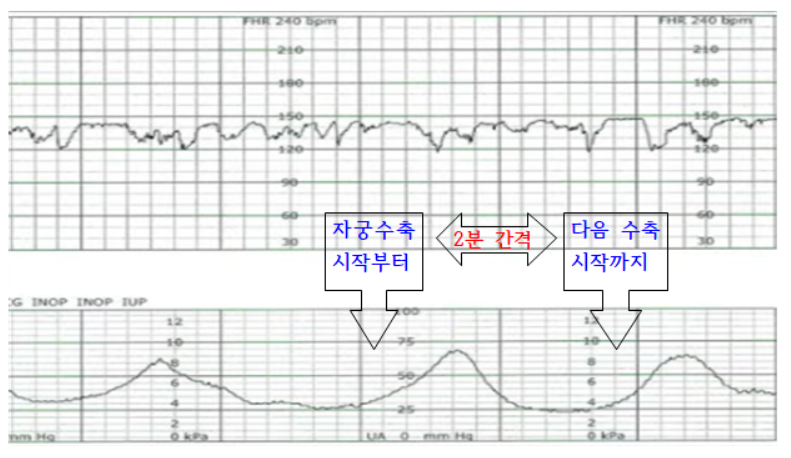

- [자궁수축Contraction]

- * 간격(interval): 자궁 수축 시작부터 다음 수축 시작까지의 시간

- 기간(duration) : 자궁이 단단하게 수축할 때부터 이완될 때까지의 시간 * 강도(intensity) : 극기의 자궁 수축 강도

- 태아 심박수 : 태아 심박수 기저선 FHR : 진통이 없는 동안이나 자궁 수축 사이의 평균 심박수로 정상범위는 120~160회/분